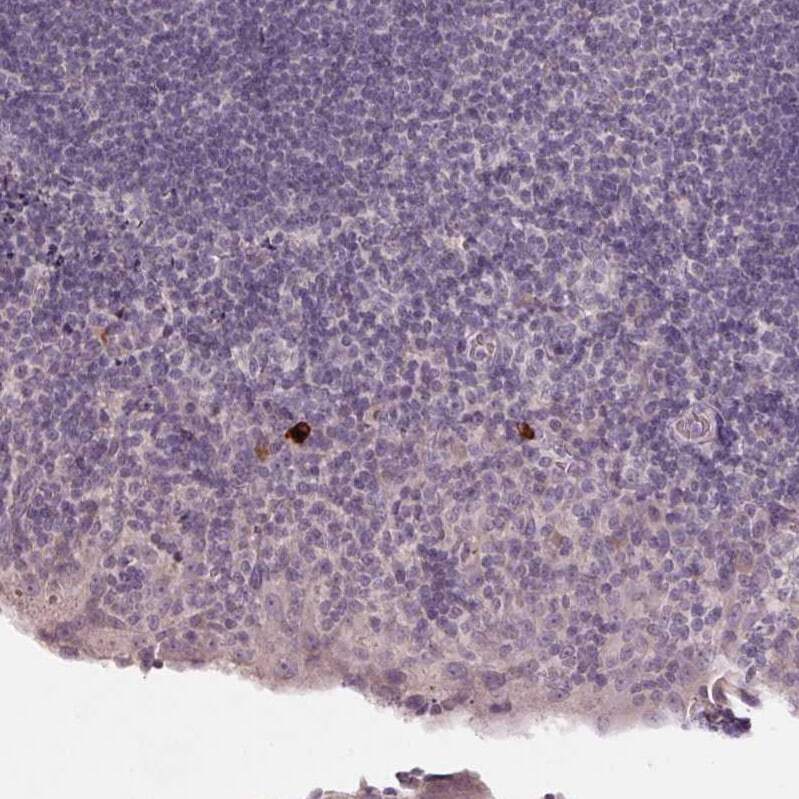

- Immunohistochemical analysis of NKG2E in human tonsil using NKG2E Polyclonal Antibody (Product # PA5-64033) shows strong cytoplasmic positivity in a subset of non-germinal center cells.